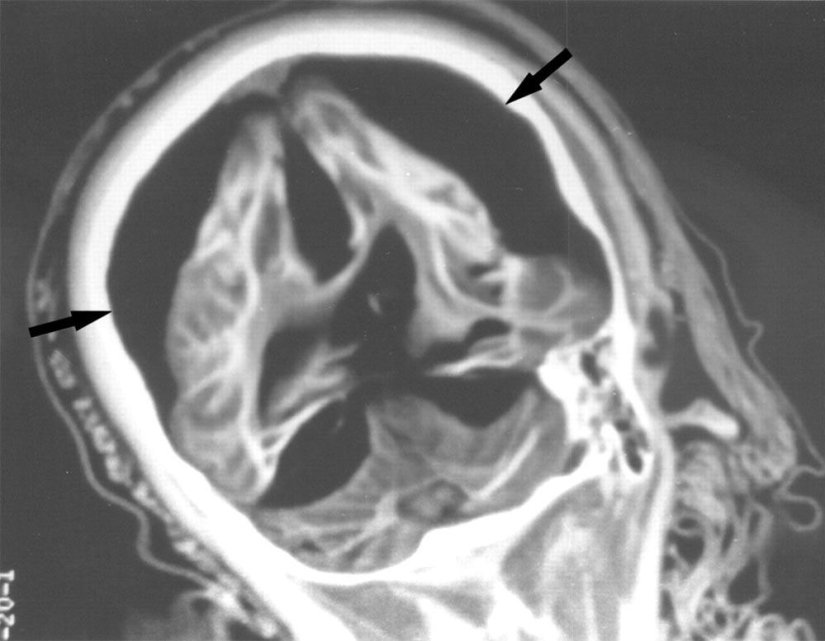

Una radiografía del cerebro de una niña de 15 años muestra que hay una separación entre la materia blanca y gris del cerebro. Las flechas apuntan al aire que rodea el cerebro.

Y esta radiografía mostró que el cerebro de un niño de 5 años estaba preservado en perfectas condiciones.